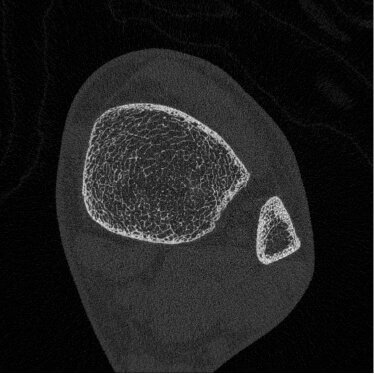

HR-pQCT装置(高解像度の末梢骨用の定量的CT装置)

高解像度末梢骨用定量的CT(high-resolution peripheral quantitative CT:HR-pQCT)は,前腕や下腿の骨を高解像度で撮影し、骨の内部構造を三次元的に評価することができる最先端計測機器です。従来の骨密度検査(DEXA)では評価しきれなかった、「骨の質」や骨の細かい構造の変化を捉えることができ、より高度な骨粗鬆症の診断・治療効果の判定に役立ちます。HR-pQCTは研究機関や専門病院など、限られた施設でしか導入されておらず、先進的な骨の評価を受けられることが当院の強みのひとつです。大学や研究機関とも共同研究を行っています。実際に患者さんの骨の状態を詳しく評価し、テーラーメードの骨の治療を行うようにしています。

【撮影画像】

-

手関節部

(20代) -

手関節部

(50代骨粗) -

足関節部

(20代) -

足関節部

(60代骨粗)